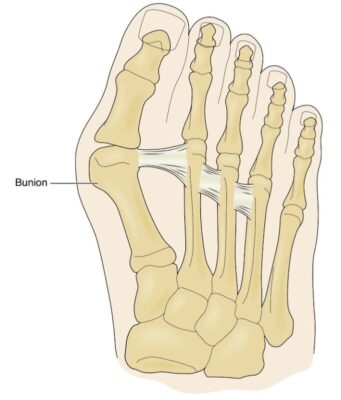

Thuật ngữ bunion bắt nguồn từ từ bunion trong tiếng Latin, có nghĩa là “củ cải”, một hình ảnh gợi ý về sự phát triển hoặc phì đại rõ ràng xung quanh khớp bàn ngón chân cái. Thuật ngữ y học cho hiện tượng này là hallux valgus, nghĩa là ngón cái vẹo ngoài.

Hallux valgus là một biến dạng phổ biến của bàn chân trước và là biến dạng phổ biến nhất của khớp bàn ngón chân cái, thường gây đau (Hình 1 và 2). Biến dạng này thường gặp ở nữ, tỷ lệ hallux valgus giữa phụ nữ và nam giới được báo cáo là 15:1.

- Khi đầu xương bàn chân lộ ra nhiều hơn, sẽ thấy rõ một cục nổi ở mặt trong, hay còn gọi là (búi) bunion. Có một bao hoạt dịch nằm giữa đầu xương bàn chân và da, và bao này có thể bị viêm và đau. Tùy thuộc vào mức độ xoay theo trục của xương bàn chân thứ nhất và độ quay sấp của ngón chân, dãy xương đầu tiên trở nên rối loạn chức năng, dẫn đến tăng chịu trọng lượng dồn lên các đầu xương bàn chân ở phía bên ngoài hơn (ngón 2, 3 …) và “đau xương bàn chân dịch chuyển” (transfer metatarsalgia), gây đau dưới mặt lòng bàn chân trước.

- Nhìn thường thấy sự phì đại rõ ràng ở trên đầu xương bàn chân thứ nhất, thỉnh thoảng có dấu hiệu viêm (viêm bao hoạt dịch). Ngón chân cái sẽ bị lệch ra ngoài, và khi biến dạng tiến triển, ngón chân cái sẽ quay sấp (xoay theo trục). Có thể có sự lệch ra ngoài của bàn chân trước và có thể có các vết chai dưới đầu các xương bàn chân của các ngón chân nhỏ hơn còn lại.